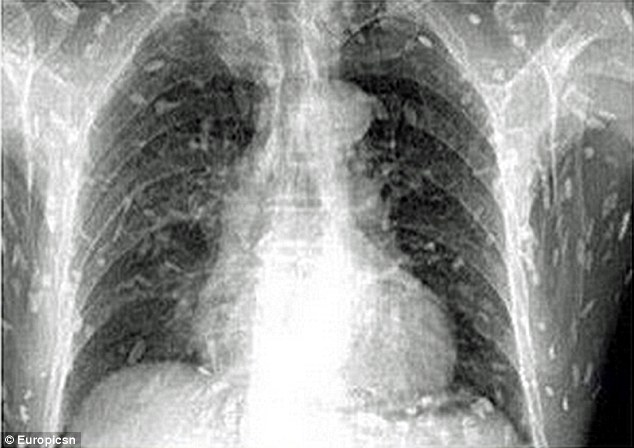

Προς έκπληξη του, οι αξονικές έδειξαν, ότι ολόκληρο το σώμα του είχε μολυνθεί με κυστοειδή σκουλήκια, επειδή έτρωγε πολύ σασίμι- ωμά κομμάτια ψαριού.

Ο άντρας από την Κίνα πήγε στον γιατρό, κάνοντας παράπονα ότι τον πονάει η κοιλιά του και έχει μεγάλη φαγούρα. Προς έκπληξη του, οι αξονικές έδειξαν, ότι ολόκληρο το σώμα του είχε μολυνθεί με κυστοειδή σκουλήκια, επειδή έτρωγε πολύ σασίμι- ωμά κομμάτια ψαριού.

Η μόλυνση από κυστοειδή σκουλήκια εμφανίζεται μετά την κατάποση των προνυμφών του διφαινυλοβαθρίου, που βρίσκονται σε ψάρια γλυκού νερού όπως ο σολομός.